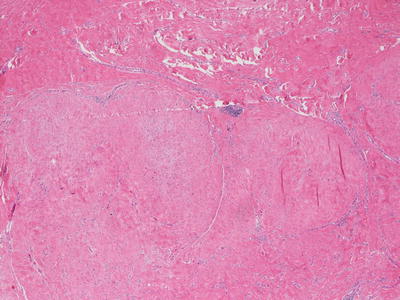

The histologic findings of a hypertrophic scar include a proliferation of fibroblasts in a nodular configuration (Figs. 25.8 and 25.9). Neovascularization is present and blood vessels are often vertically oriented within the dermis. The epidermis may be flattened with loss of rete ridges, as well as loss of appendages in the areas of fibroblastic proliferation. The cellularity of the lesion varies with its age. In early hypertrophic scar, there are abundant small vessels and dermal fibroblasts, while in late stage lesion the number of cells in the dermis is much lower. The fibroblasts retain an orientation that is parallel to the surface of the skin in most cases. Elastic tissue fibers are markedly diminished within the area of new collagen formation.

Fig. 25.8

A hypertrophic scar demonstrates a lobular appearance within the dermis. The epidermis is often flattened and there is loss of cutaneous appendages in the region of the scar

Fig. 25.9

Lobules of new collagen can be distinguished from the background native collagen in a hypertrophic scar, and may resemble the lobularity seen in a leiomyoma